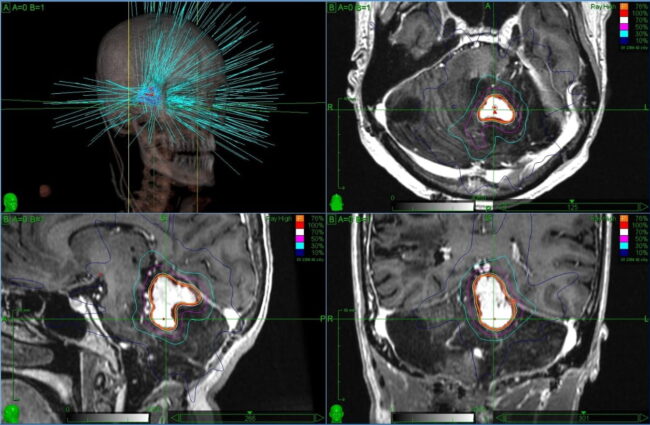

Análisis del conectoma del núcleo accumbens: refinando la diana de la radiocirugía para los trastornos adictivos. Jose E. Chang. William O. Contreras Lopez. Richard Gonzalo Párraga .Jorge Torres Monterrosa. Larissa Merlos Salazar. Eduardo E. Lovo Resumen Esta investigación estudia las conexiones del núcleo accumbens (NAc) para mejorar la precisión de la rad/cirugía estereotáxica (radiosurgery) como…